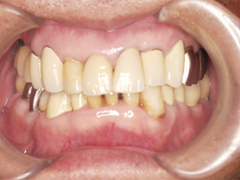

1.インプラント治療(きちんと噛めるように長いインプラントと短いインプラントを組み合わせ治療を行う)

2.マウスピースによる咬合改善維持

3.定期的な予防治療(PMTC)

骨が少なくとも、サイナスリフトという大掛かりな外科手術を行なわずにインプラント治療が実現することができました。